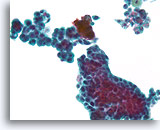

Papillair neoplasma, Borst FNA, Celblok.

Een kleine vergroting van de residuele naaldspoeling van de patiënt in afbeelding 39-42 toont een duidelijk papillaire architectuur. Let op de gelijksoortigheid van de ductale populatie in dit hele veld. Dit monotone patroon duidt meer op een papillair carcinoom dan een papilloom.

Papillair neoplasma, Borst FNA, Celblok.

Een kleine vergroting van de residuele naaldspoeling van de patiënt in afbeelding 39-42 toont een duidelijk papillaire architectuur. Let op de gelijksoortigheid van de ductale populatie in dit hele veld. Dit monotone patroon duidt meer op een papillair carcinoom dan een papilloom.